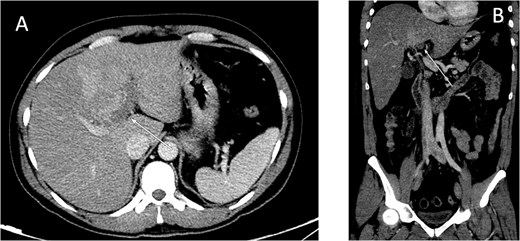

An ultrasound of the abdomen showed an impacted stone at the neck of the gallbladder with acute cholecystitis. The patient was admitted and started on IV antibiotics. He developed tachycardia reaching 110 bpm and had a high white blood cell count; therefore, the decision was made to proceed with a contrast-enhanced computed tomography (CT) scan, which showed evidence of acute cholecystitis and left PVT (Fig. 1). The medical team was consulted, and IV heparin without bolus was started. The gastroenterology team was consulted for his high bilirubin levels and advised for magnetic resonance cholangiopancreatography (MRCP), which was done the next day and confirmed the findings of left PVT (Fig. 2). MRCP also showed a micro perforation of the gallbladder and no biliary obstruction or stones (Fig. 3).

Axial cut MRCP showing T2-weighted images. Arrow indicates area of micro-perforation and small collection.